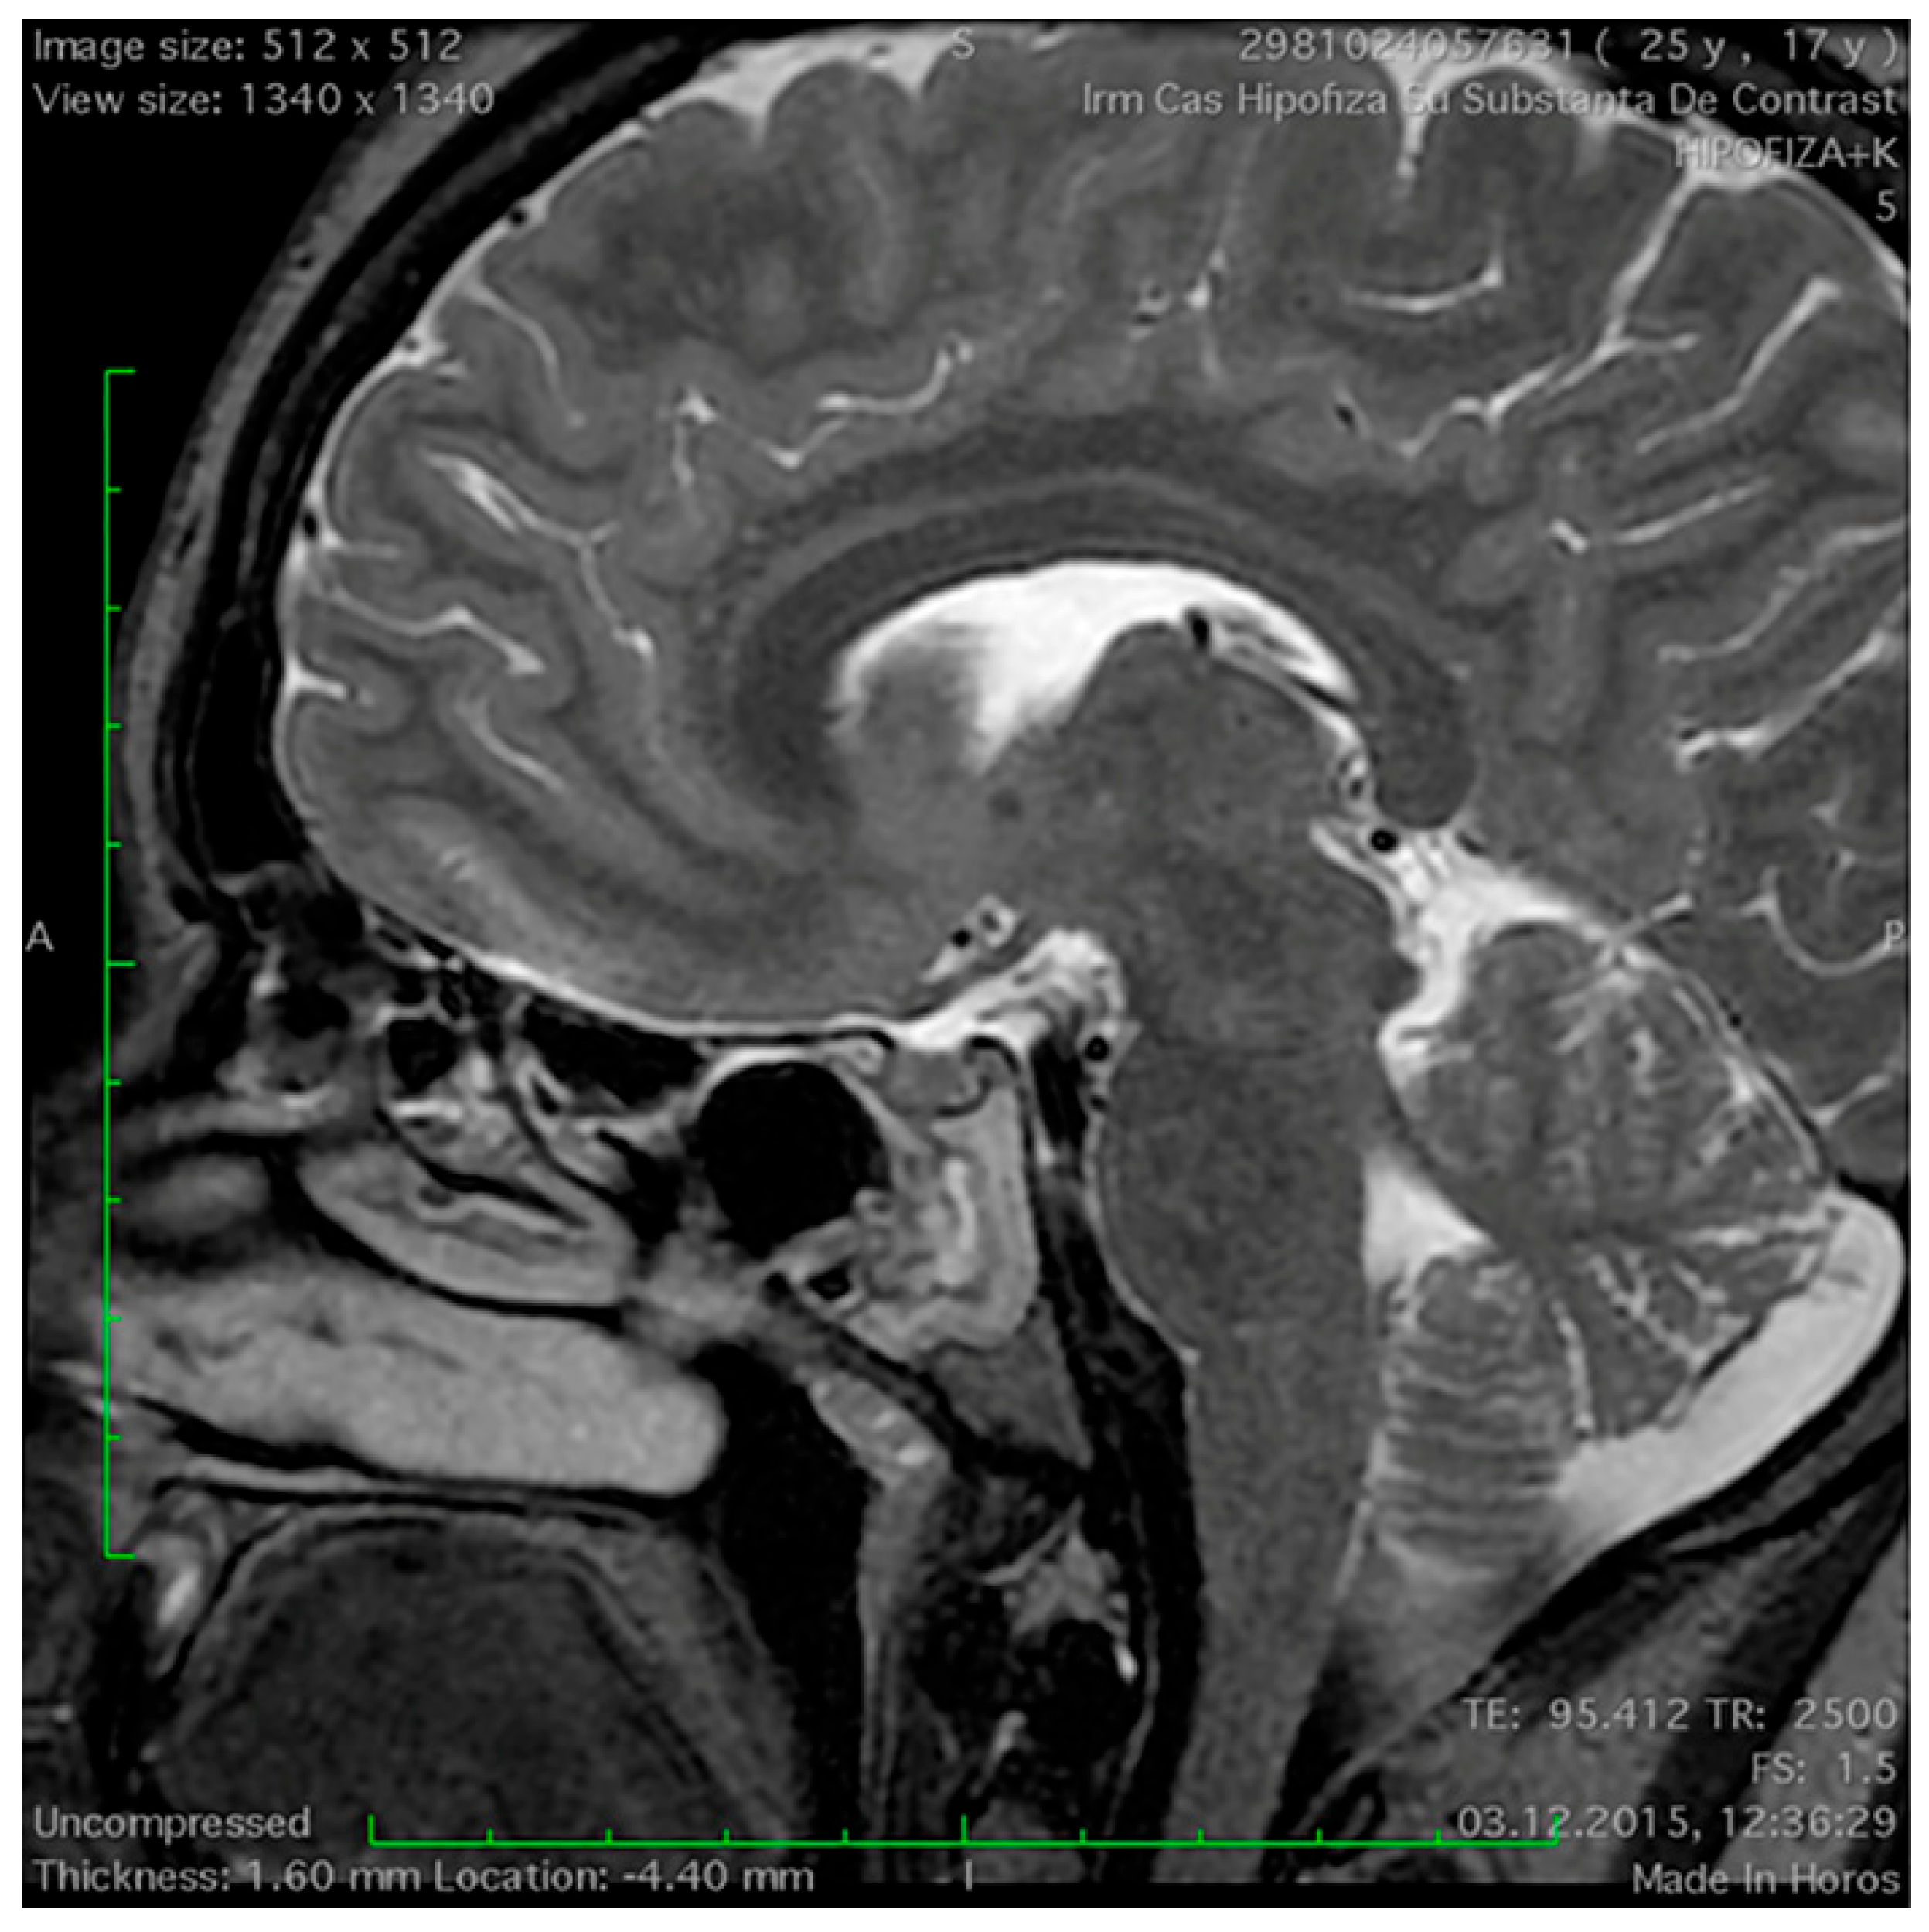

Magnetic Resonance Imaging Features of the Sphenoid Sinus in Patients with Non-Functioning Pituitary Adenoma

2.2. Magnetic Resonance Imaging Study